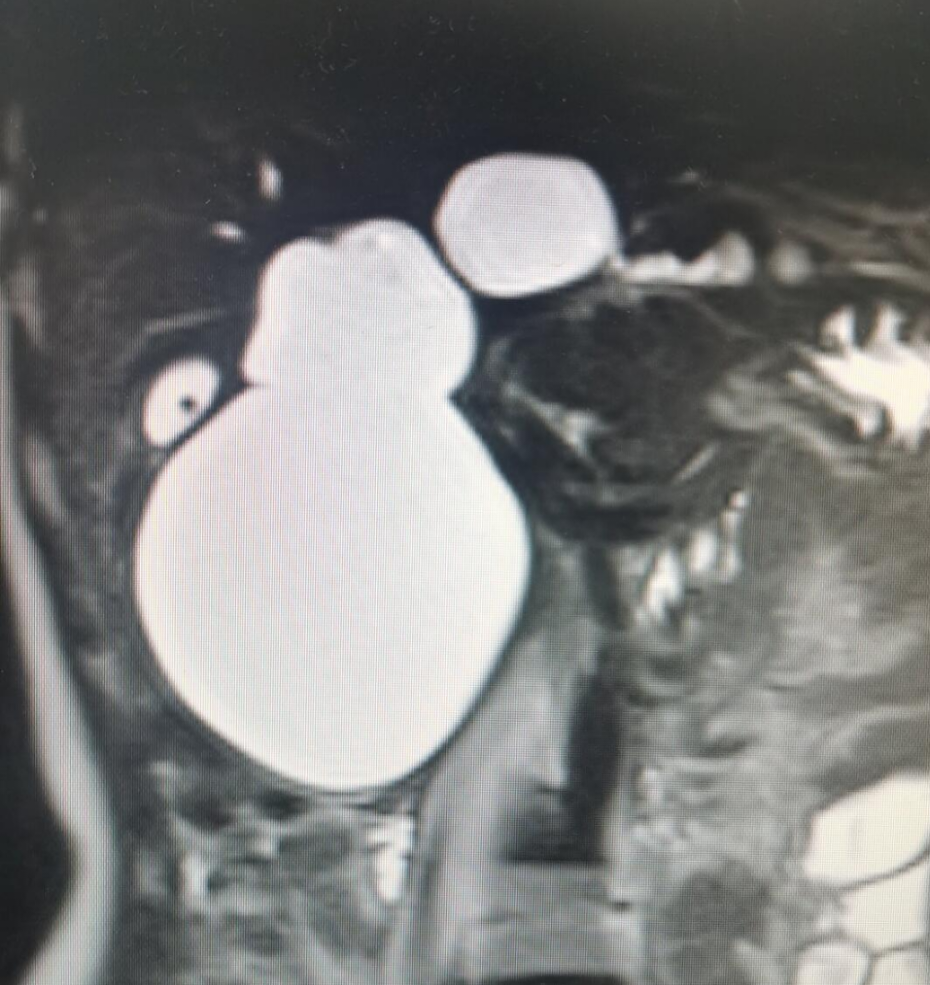

先天性胆总管囊肿。患者为先天性胆总管囊肿,左肝内及右肝内部分胆管囊肿扩张,腹部疼痛多年,近期疼痛发作频繁。多地就医,均考虑开腹手术,经既往患者推荐,慕名来找我就诊。综合考虑,年轻女性,腹腔镜手术为最佳方案。考虑左肝胆管囊肿扩张较右肝明显,扩张部位多,术前规划腹腔镜先天性胆总管囊肿切除+左半肝切除。胆总管囊肿一般为先天性,常合并腹痛等胆管炎症状。病史长,可能出现癌变,手术是唯一方案。出现症状早,婴幼儿期就可以手术治疗。成年人诊断明确,应该积极手术,既往有发现后没有及时手术处理,最终癌变,导致不良后果。目前方案腹腔镜手术安全可靠,腹部切口小,恢复快。术后1周左右可以出院。